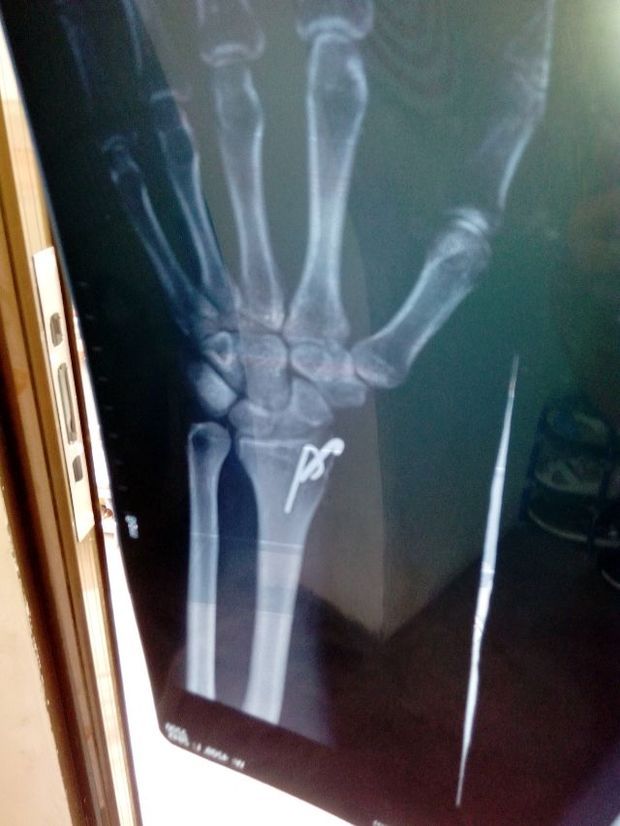

右手桡骨远端骨折,对位尚可。 但是觉得接得不

右手桡骨远端粉碎性骨折